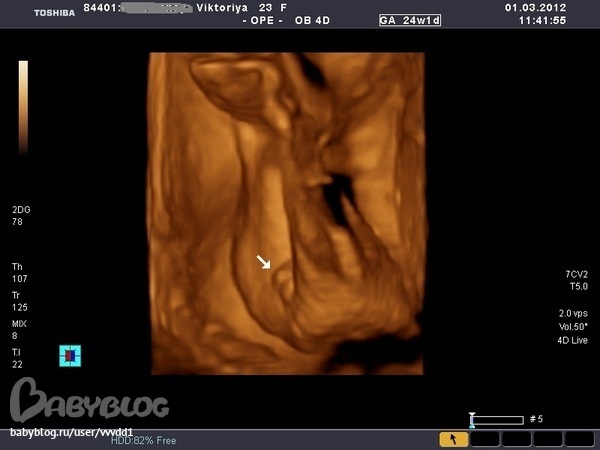

Результаты: УЗИ, КТГ, доплера, скринингаОчень понравилось,столько эмоций))))Пока мы ехали в больницу я слопала сникерс и уже в пути я начала ощущать пиночки.На узи нам подтвердили,что девочка.Малышка наша такая скромница, ручками глазки закрывала,пальчик сосет, а потом как дала боксом заниматься.Записали на диск видео, дали кучу фоток.Папа наш сидел,все налюбоваться не мог, говорит что она так на меня похожа.Весит наша принцесса 650 г.Врач очень хороший,много рассказывал,плацента поднялась,никаких аномалий развития не выявлено,Боже,как я попереживала за эту плаценту,как я рада,что все обошлось,а вот собственно и фотки нашего счастья